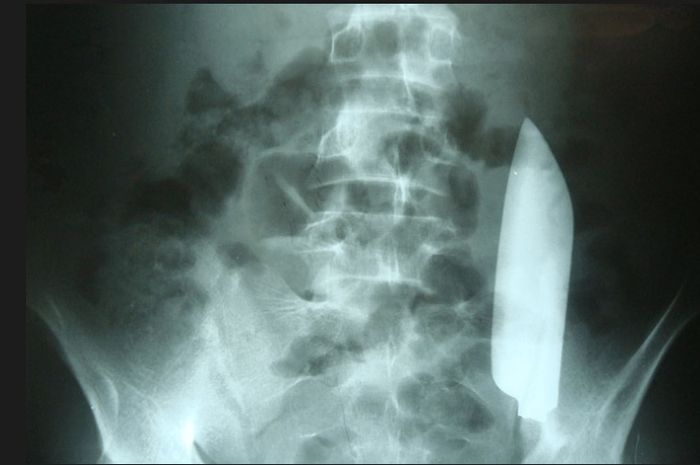

Bukan penyakit yang ditemukan namun justru ada pisau sepanjang 15 cm yang 'bersemayam' di dalam perutnya.

Setelah dilakukan rontgen, dokter kemudian menemukan ada pisau besar masih ada di dalam dan posisinya melintasi perutnya dari sisi kanan ke kiri.

Tampaknya pisau tersebut tidak melukai organ dalam lainnya, menurut laporan kasus di jurnal Cureus, 2 September 2023.

Meskipun demikian, kondisi tersebut bisa berakibat fatal jika tidak segera ditangani.

“Ini merupakan kondisi yang berpotensi mengancam nyawa jika pisau berada dekat dengan organ vital di perut,” kata laporan kasus tersebut.